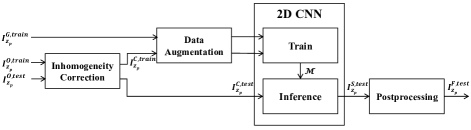

Figure 1 shows a block diagram of the proposed method. We denote a 3D image volume of size by , and the focal plane image along the -direction, of size pixels, by where . We also denote the original training and test images in the focal plane by and , respectively. In addition, and denote the groundtruth images that are used for training and testing that correspond to and , respectively. Similarly, and denote inhomogeneity corrected training and test images, respectively. Lastly, denotes the binary segmentation mask generated by our proposed deep learning architecture and denotes the final segmentation outcome. For example, the original focal plane is denoted as , its corresponding groundtruth image by , the inhomogeneity corrected version by , the binary segmentation mask as , and the final segmentation result by , respectively.

As shown in Figure 1, our proposed network includes two stages: a training and an inference stage. During the training stage original training images () have their intensity inhomogeneities corrected () as a preprocessing step. Since fluorescence microscopy images suffer from intensity inhomogeneity due to non-uniform light attenuation, correcting intensity inhomogeneity helps improve final segmentation results. We then utilize both and as inputs to the data augmentation step to increase the number of training image pairs used for training the CNN model, . During the inference stage inhomogeneity correction is done on the test images () to obtain . These are then used to segment tubules with the trained model .